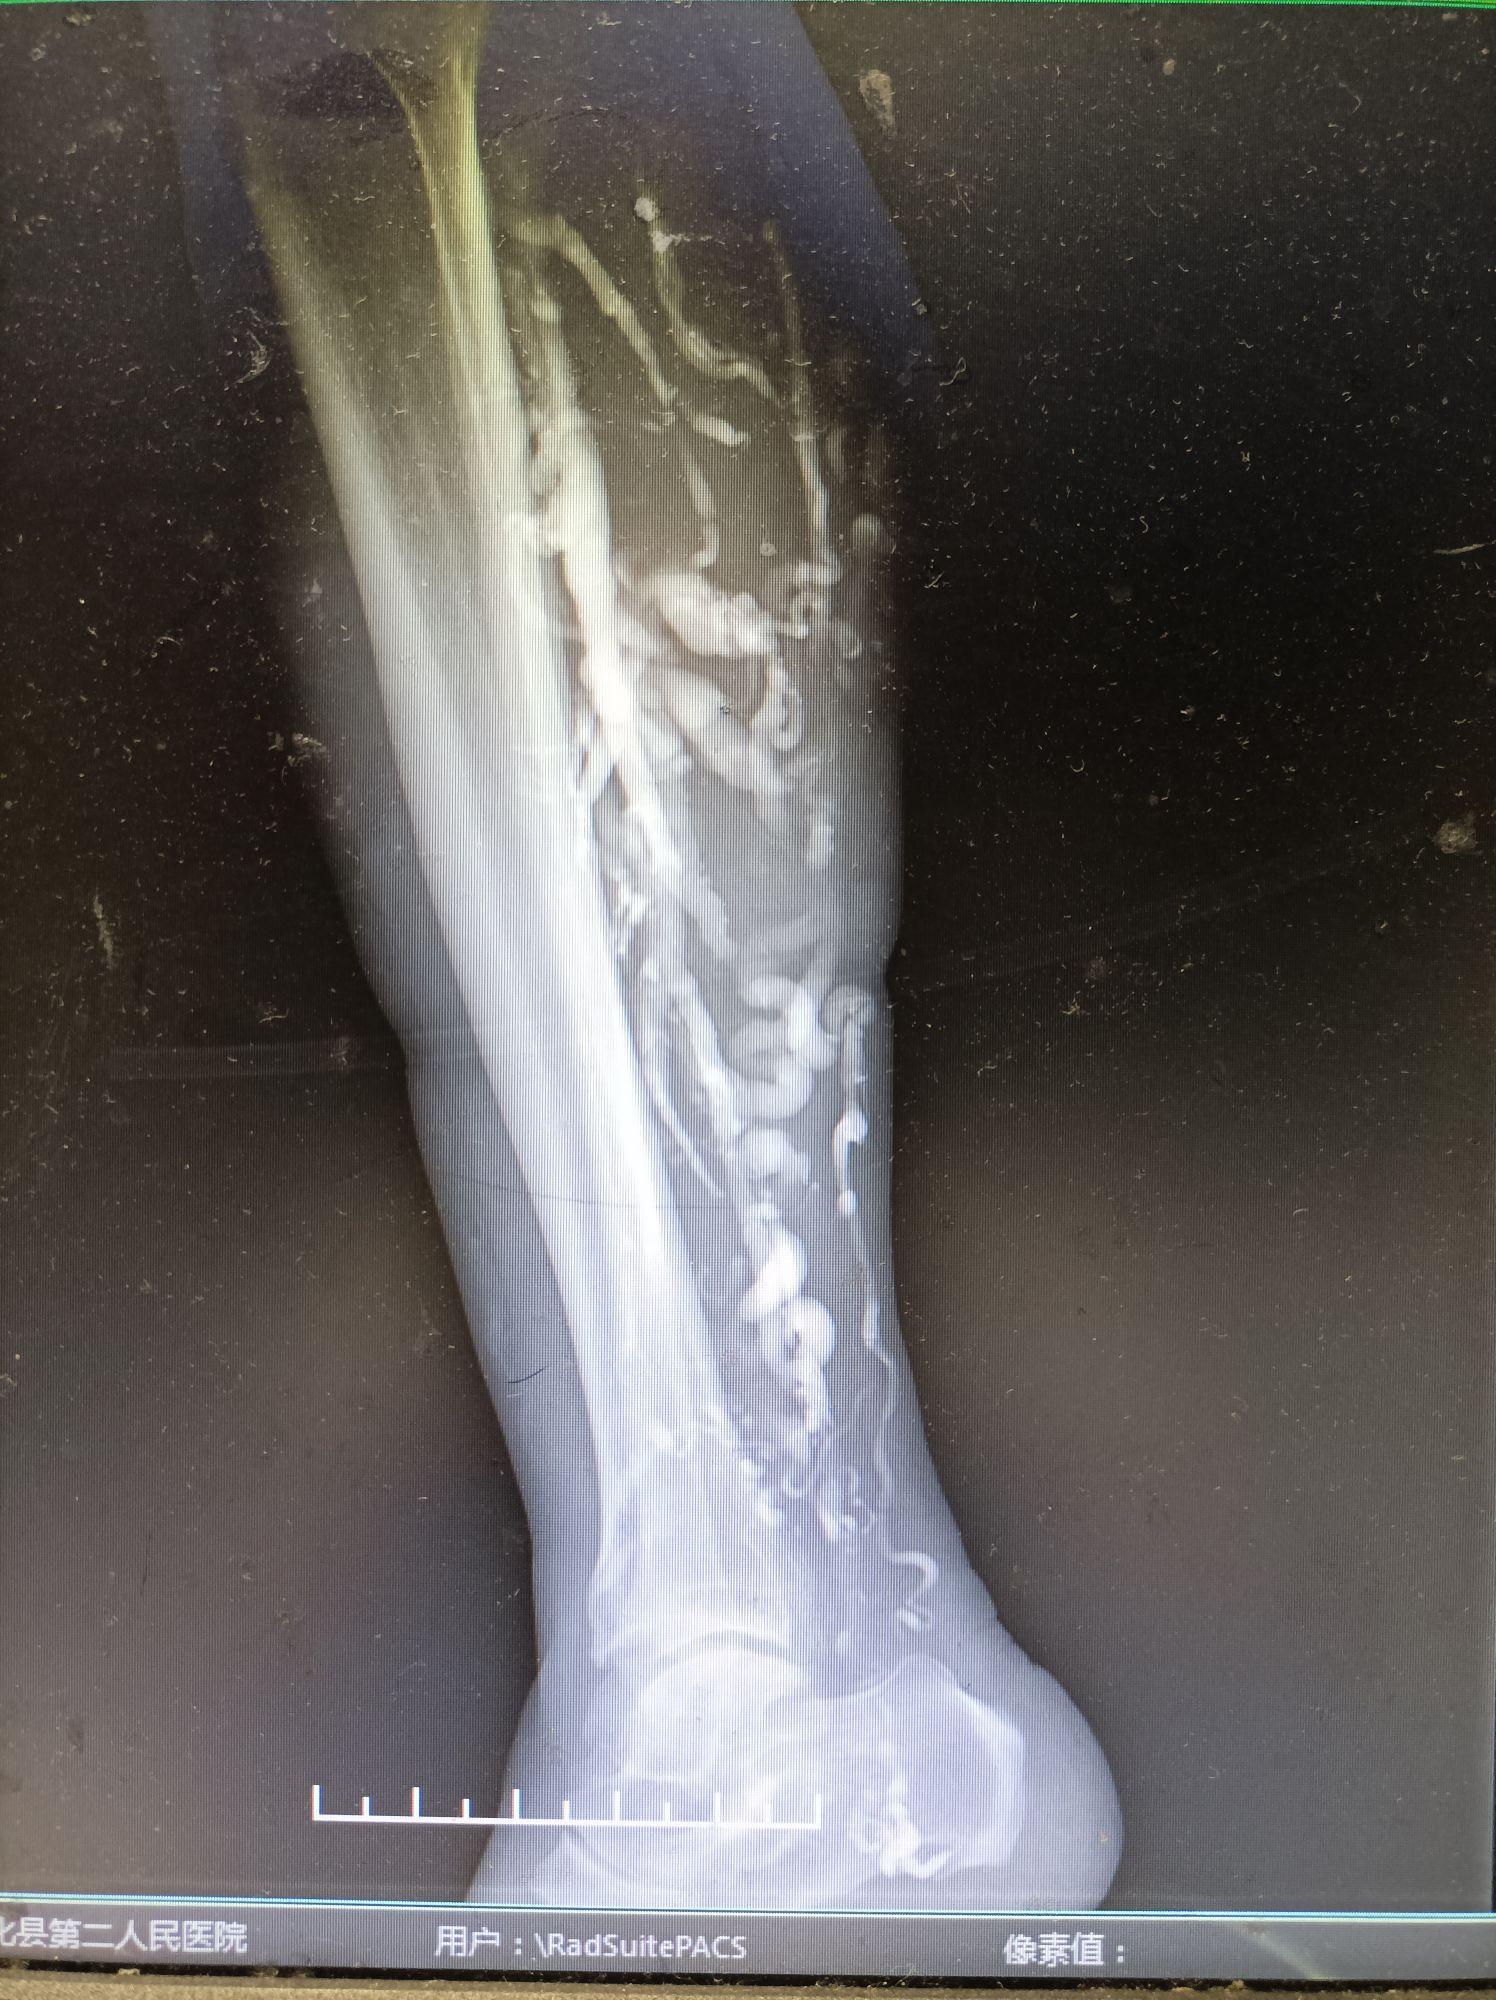

超聲檢查:是首選的初篩工具,可顯示淺靜脈曲張、深靜脈發(fā)育異常(如缺如、狹窄)及部分淋巴管擴(kuò)張,但對(duì)深層結(jié)構(gòu)(如骨骺生長(zhǎng)板受刺激情況)及微小淋巴管缺如的分辨率不足;

MRI/MRA:能清晰顯示軟組織增生、骨骼長(zhǎng)度差異及深靜脈走行,但對(duì)淋巴管的直接成像仍依賴間接征象(如皮下組織增厚伴信號(hào)異常),且檢查時(shí)間長(zhǎng)、兒童配合度低。

淋巴造影:理論上可直觀評(píng)估淋巴管通暢性,但因有創(chuàng)性(需注射造影劑至皮內(nèi)淋巴管)和并發(fā)癥風(fēng)險(xiǎn)(感染、過敏),臨床極少常規(guī)開展。